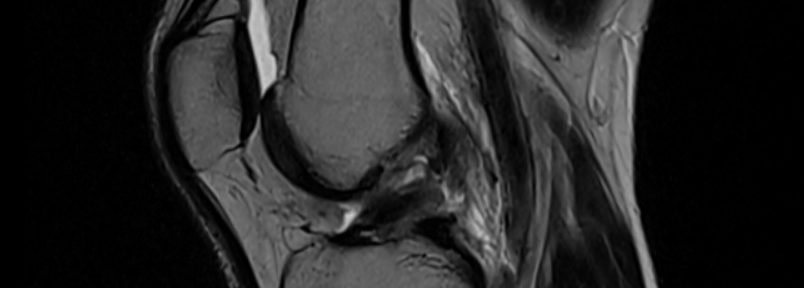

- MRI撮影日(初回):2022年12月22日

- 診断名:左膝前十字靭帯完全断裂

MRI診断(治療前):2022年12月22日

3名の独立した画像診断専門医がIhara分類に基づき評価。

- Ihara分類:2名がⅢ型(完全断裂、断端の転移)、1名がⅡ型(完全断裂、断端の転移なし)